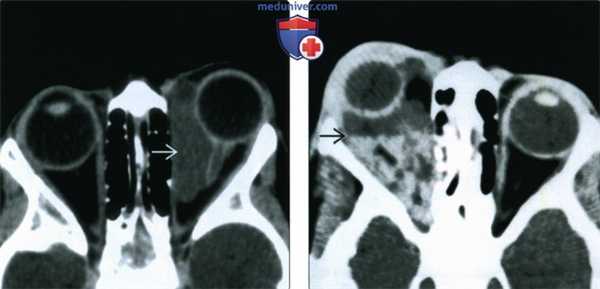

(Слева) При КТ с КУ в аксиальной проекции в медиальной части левой глазницы определяется кистозное четко отграниченное неконтрастируемое образование, стенка образования неразличима. Хотя наблюдается картина простого однокамерного образования, оно лежит в нескольких смежных пространствах, имеет пресептальный компонент и компоненты внутри и вне мышечного конуса.

(Справа) При КТ без КУ в аксиальной проекции у четырехлетнего ребенка определяется неправильной формы многокамерная лимфатическая мальформация глазницы, распространяющаяся в несколько смежных пространств. Расслоение жидкостей с различными плотностями обусловлено оседанием продуктов распада крови, скопившихся при спонтанном кровоизлиянии.